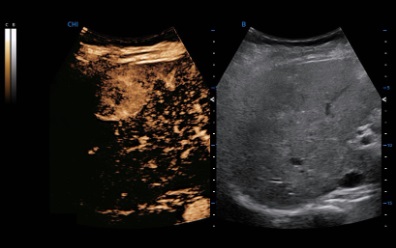

CHI

Fewer contrast agents needed, SIUI’s Contrast Harmonic Imaging delivers uniformed image quality and longer duration. Common probes are enough to obtain strong penetration with CHI.